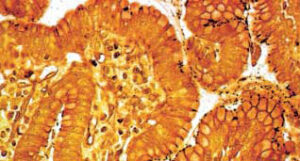

Gli esami e la diagnosi | È possibile porre una diagnosi di infezione da Helicobacter pylori mediante metodi invasivi o non invasivi. Uno dei metodi invasivi è il prelievo di mucosa gastrica durante un esame endoscopico, per farla analizzare con test dell’ureasi, con esame istologico, coltura in piastra o con PCR. Per quanto riguarda i test non invasivi, il più semplice è il test del respiro (Urea Breath Test), effettuato somministrando oralmente dell’urea marcata con un isotopo e misurandone la concentrazione nell’aria respirata, emessa soffiando in una provetta. La ricerca di anticorpi, invece, può essere effettuata mediante analisi del sangue, della saliva, delle feci, dell’urina, mentre la ricerca degli antigeni si effettua con test.